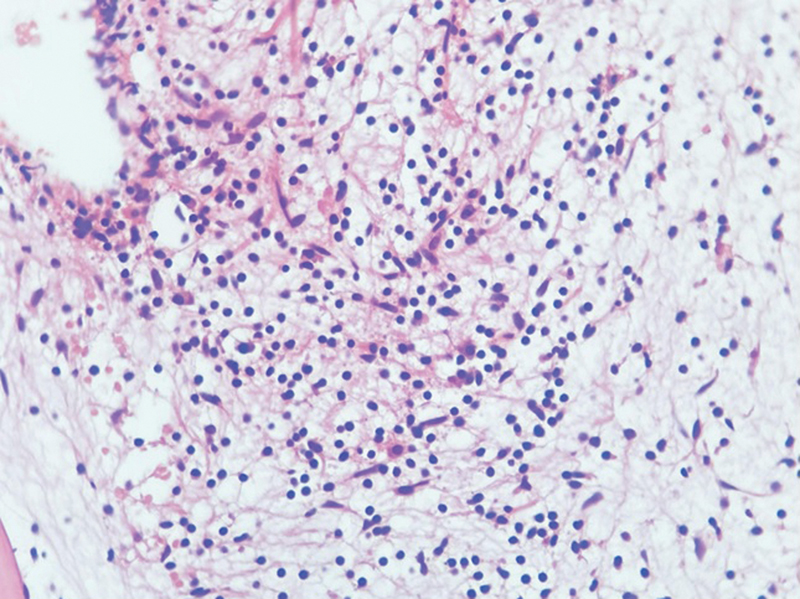

Initial examination was unremarkable except palpable hepatomegaly 2 cm below the right costal margin. There was no lymphadenopathy or other significant findings. Preliminary investigations were similar to outside reports, with no abnormal cells noted on peripheral smear. Liver and renal function tests and autoimmune markers were negative. A bone marrow examination was repeated, which again resulted in a dry tap. Trephine biopsy revealed a hypocellular marrow with a cellularity of 10 to 20%. associated with absent megakaryocytes and grade 2 to 3 reticulin fibrosis ([Figs. 1] and [2]). On further sections, interstitial infiltrates of small-sized lymphoid cells with round, clumped chromatin and inconspicuous nucleoli were noted. These cells were positive for CD20 and BCL2, and negative for CD5, CD10, BCL6, annexin A1, cyclin D1, and TdT on immunohistochemistry (IHC). Fluorescent in situ hybridization (FISH) panel for MDS and next-generation sequencing (NGS) for myeloid mutations were initially sent, both of which were negative.

Fig. 2 High power view of bone marrow trephine biopsy showing small lymphoid cells and grade 2–3 fibrosis. H&E, 400X.